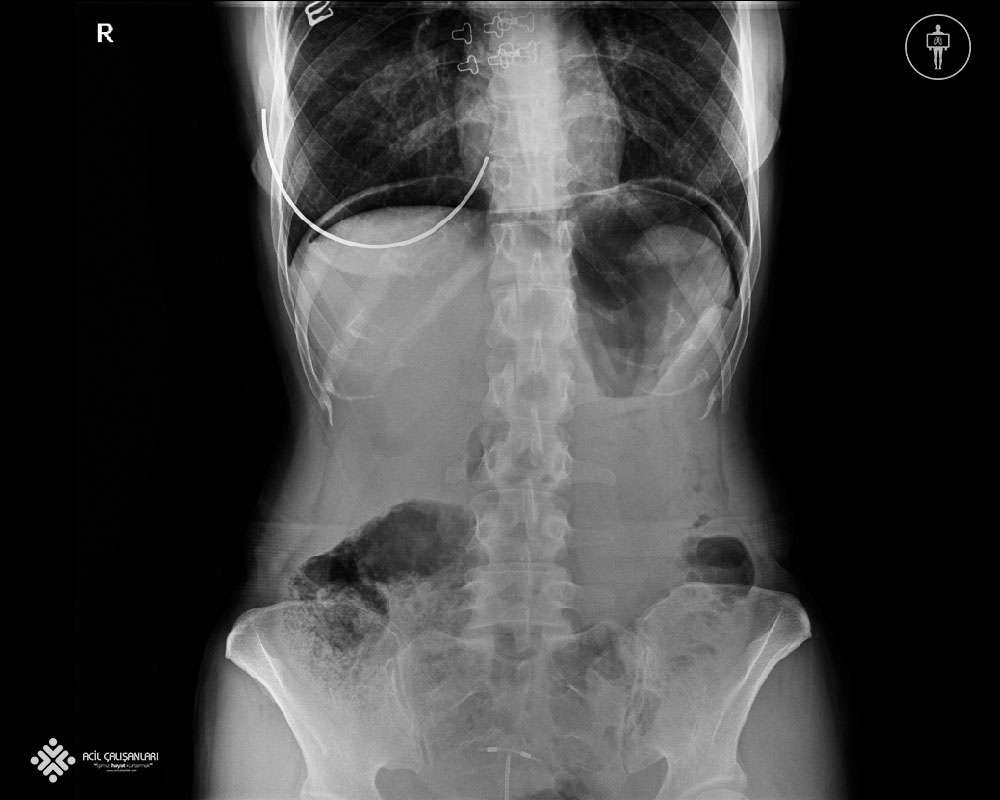

40 yaşında bayan hasta karın ağrısı şikayeti ile acil servise ayaktan başvuruyor. Triaj alanında değerlendirilen hastanın; Genel durumu iyi, Vitalleri: Nabız: 92atım/dk düzenli ; Solunum: 18/dk ; SpO2: 96 ; Kan Basıncı: 100/60 mm/Hg olarak değerlendiriliyor ve yeşil alana yönlendiriliyor. Yaklaşık 20 dakika sonra yeşil alan dokturu tarafından muayene edilen hastanın fizik muayenesinde batında epigastrik bölgede hassasiyet saptanıyor. Gebelik şüphesi olmayan, operasyon öyküsü olmayan, defansı ve reboundu olmayan, gün içerinde gaz gaita çıkışı olan hastadan hemogram, geniş biyokimya ve ayakta direkt batın grafisi ( ADBG) isteniyor. Hasta hızlıca rörtgene alanına gidiyor ve grafisi çektiriyor. Ağrıları artan hasta sıra beklemek istemiyor ve grafisinin bir an önce değerlendirilmesini istiyor ve tekrar doktoruna başvuruyor. Aşağıda grafisi görünen hastaya sizce bundan sonraki yaklaşım ne olmalıdır ve aşamalarıyla doğru olan seçenek hangisidir ?

E) Grafide diyafram altında serbest hava görüntülenmektedir. Acil genel cerrahi konsültasyonu istenmeli, bu sırada hastaya nazogastrik (NG) tüp takılarak mide dekompresyonu sağlanmalı ve oral alımı kesilmelidir.

Hastamızda ADBG’sinde  diyafram altında serbest hava görünmekte  buda bize gastrointestinal perforasyonu düşündürmektedir. Gastrointestinal kanal perforasyonu peptik ülser hastalığı, travma, iyatrojenik, yabancı cisim, apandisit, enflamasyon, tümör gibi nedenlerle ortaya çıkmakta ve erken tanı ve zamanında cerrahi müdahale  ile mortalitesi ve morbitesi  oldukça azalmaktadır. Gastrointestinal kanal perforasyonnları mortal seyrettiği için gözlem alıntında tutulmalı, oral stoplanmalı ve ana tedavi yöntemi cerrahi olduğu için hasta bir an önce genel cerrahiye danışılması gerekmektedir. Ayakta batın grafisi acillerde, akut karın ağrılarının değerlendirilmesinde ayakta batın grafisi sık olarak istenmektedir.  Akut karın ağrısının tanısal incelemesinde akciğer ve karın grafilerinin yeri ile ilgili yapılan yayınlarda, grafilerin tanı konulmasındaki etkinliklerinin ve tedaviyi yönlendirmelerinin oldukça kısıtlı olduğu, akut karın ağrısı şikayeti ile acil servise başvuran her hastadan direkt grafi tetkiki istenilmesi halinde, tanıya yardımcı patolojik bulgu elde edilme oranı ortalama %10 olduğu gözlemlenmektedir. Bu yüzden acil cerrahi hastalıklar arasında en sık intestinal obstrüksiyon ve gastrointestinal perforasyon için karın grafilerinin tanısal etkinliği etkinliğe sahiptir. Bu yüzden klinik ve fizik muayene bulguları intestinal obstrüksiyon ve gastrointestinal perforasyon lehine değerlendirilen hastalarda direkt karın grafisi ilk tetkik olarak istenmelidir. Ancak, akut apandisit dâhil diğer akut karın patolojilerinde direkt karın grafilerinin kullanılması yetersiz tanısal etkinlik ve radyasyon riski açısından uygun gözükmemektedir.